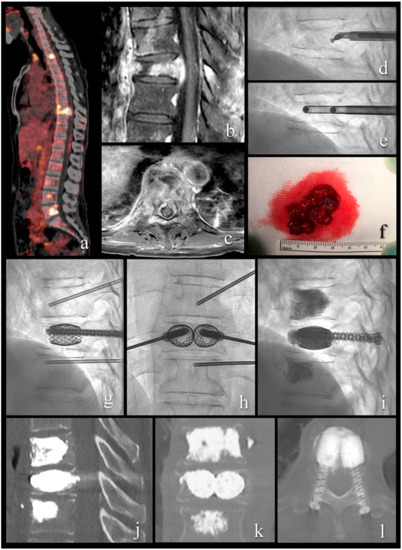

Mechanical Cavity Creation with Curettage and Vacuum Suction (Q-VAC) in Lytic Vertebral Body Lesions with Posterior Wall Dehiscence and Epidural Mass before Cement Augmentation

Procedural Details